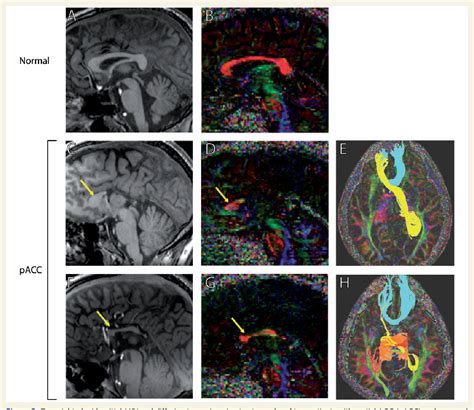

The concept of neuroplasticity is perhaps the most hopeful aspect of managing this condition. Research suggests that when the corpus callosum is absent, the brain often develops "Probst bundles," which are bundles of nerve fibers that run longitudinally rather than crossing the midline. This allows the hemispheres to maintain some level of communication. Furthermore, the anterior and posterior commissures—smaller structures that connect the brain hemispheres—may enlarge to take on a larger share of the workload.

• corpus callosum agenesis mri